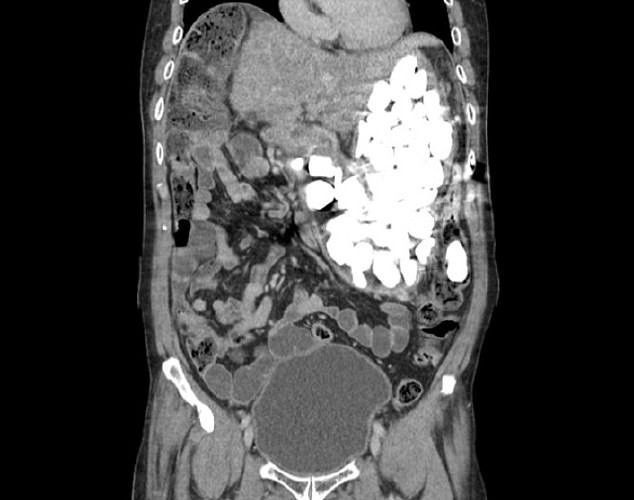

İlginç olay Güney Kore'de gerçekleşti. Adam ağır mide ağrısı ve şişkinlik nedeniyle hastaneye başvurdu. Birkaç tetkikin ardından adamın midesinde yabancı cisimler tespit edildi.

Doktorlar elle yaptıkları muayenelerinde de küçük taşlar hissettiklerini söylediler. Operasyonun ardından adamın midesinden iki kilogram ağırlığında taş, şişe kapağı ve bozuk para çıkarıldı. Tüm olaylardan sonra asıl ilginç olan ise adamın yaptığı açıklama oldu.